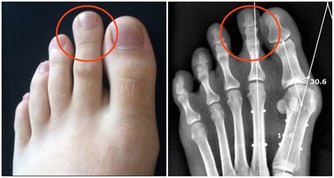

那麼,怎麼才能知道你是否有靜脈曲張呢?很多人覺得靜脈曲張很好辨認,因為你能看到腿部出現突出的凸出靜脈,跟蚯蚓似的。根據靜脈曲張的深度,那些“蚯蚓”可能是藍色、綠色甚至無色。

然而,在出現並發症之前,多達一半的靜脈曲張患者都沒有明顯的病情跡象,因為許多有問題的靜脈仍隱藏在皮膚下,在檢查中才可以看到。但如果你仔細觀察,憑藉肉眼,我們也能發現靜脈曲張的跡象。